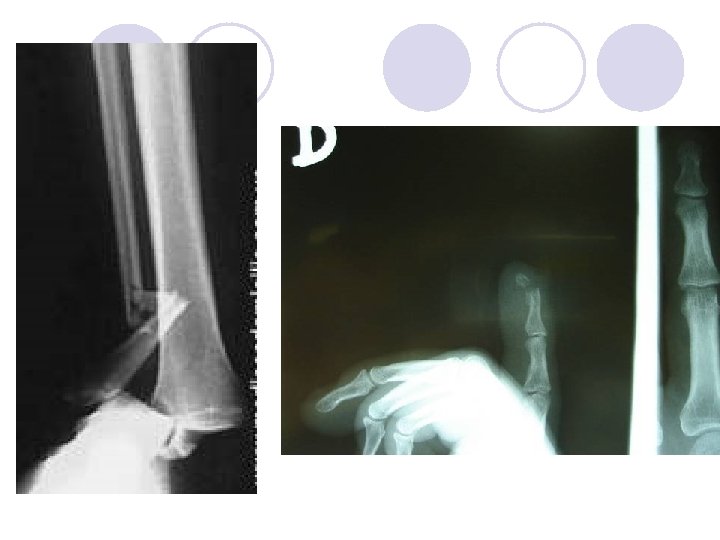

FRACTURAS Definición: “solución de continuidad, parcial o total de un hueso. ” Continuidad estructural Energía Elasticidad ósea Hematoma de fractura Etiología (causa) Predisponentes Determinantes Tipos de fracturas (Clasificaciones)

Amputación • Es la pérdida parcial o completa de una extremidad como: un dedo, una mano, un brazo, pie, etc. Aplastamiento • Cuando las partes del cuerpo son atrapadas por objetos pesados. Pueden incluir fracturas óseas, lesiones a órganos externos y a veces hemorragias externa e interna abundantes.